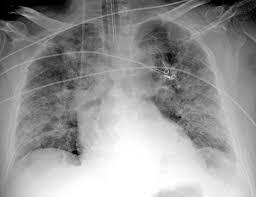

Treatment of throat cancer is based on its location, type of cancer, stage, and your child's health status. And by the time matthew's ameloblastoma was detected, his tumor was the size of a golf ball. The tumor may be any size, but it has spread to: Lung cancer tumors look like white round circles on cxr. To evaluate respiratory conditions like asthma, bronchitis, and pneumonia, heart conditions, broken ribs, and to look for fluid and tumors within the chest cavity. Sometimes doctors can see a tumor around the defect in the bone that might extend into nearby tissues (such as muscle. Each subtype of throat cancer has its own criteria for each stage. A bumpy spot near the front teeth. Oral cancer may present as: Throat cancer refers to cancer of the voice box, vocal cords, and other parts of the throat, such as the tonsils and the oropharynx. In some cases, doctors will notice a tumor around that particular area of the bone. The appearance of throat cancer on the other hand depends on the part of the throat that is affected by cancer and the stage of its development. Surgical complications and side effects arising out of throat cancer treatment.

The cancer can also appear as a hole in the bone. The lungs look black because they are filled with air. If you notice the second tooth from the left, you can see a dark aura surrounding the tip of the root. Lung cancer tumors look like white round circles on cxr. And if this isn't cancer, could anybody offer an explanation as to what would cause a sore throat and growing lump?

For patients diagnosed with throat cancer, a pet/ct scan may be used to see if cancer has spread to the lymph nodes, to determine the origin of cancer when it is found in the lymph nodes first, or to check the body for the spread of cancer cells. The lungs look black because they are filled with air. Any time your cat has stopped eating normally, you should make an appointment with your veterinarian. If this cessation of normal eating is accompanied by changes in the voice, contact your veterinarian immediately. Like every other type of surgery, throat cancer surgery also carries extensive risks such as the possibility of blood clots, infections, complications arising out of anaesthesia, and even pneumonia. While the jaw pain alerted him that something was wrong, the condition isn't visible. Throat cancer may also look like unusual white patch of tissue termed as leukoplakia. Also, would throat cancer cause a lump like this growing on the outside of the throat/neck? If the fna shows cancer, the pathologist (the doctor examining the samples) can often tell what type of cancer it is. Lung cancer tumors look like white round circles on cxr. And if this isn't cancer, could anybody offer an explanation as to what would cause a sore throat and growing lump? Each subtype of throat cancer has its own criteria for each stage. In some cases, doctors will notice a tumor around that particular area of the bone.